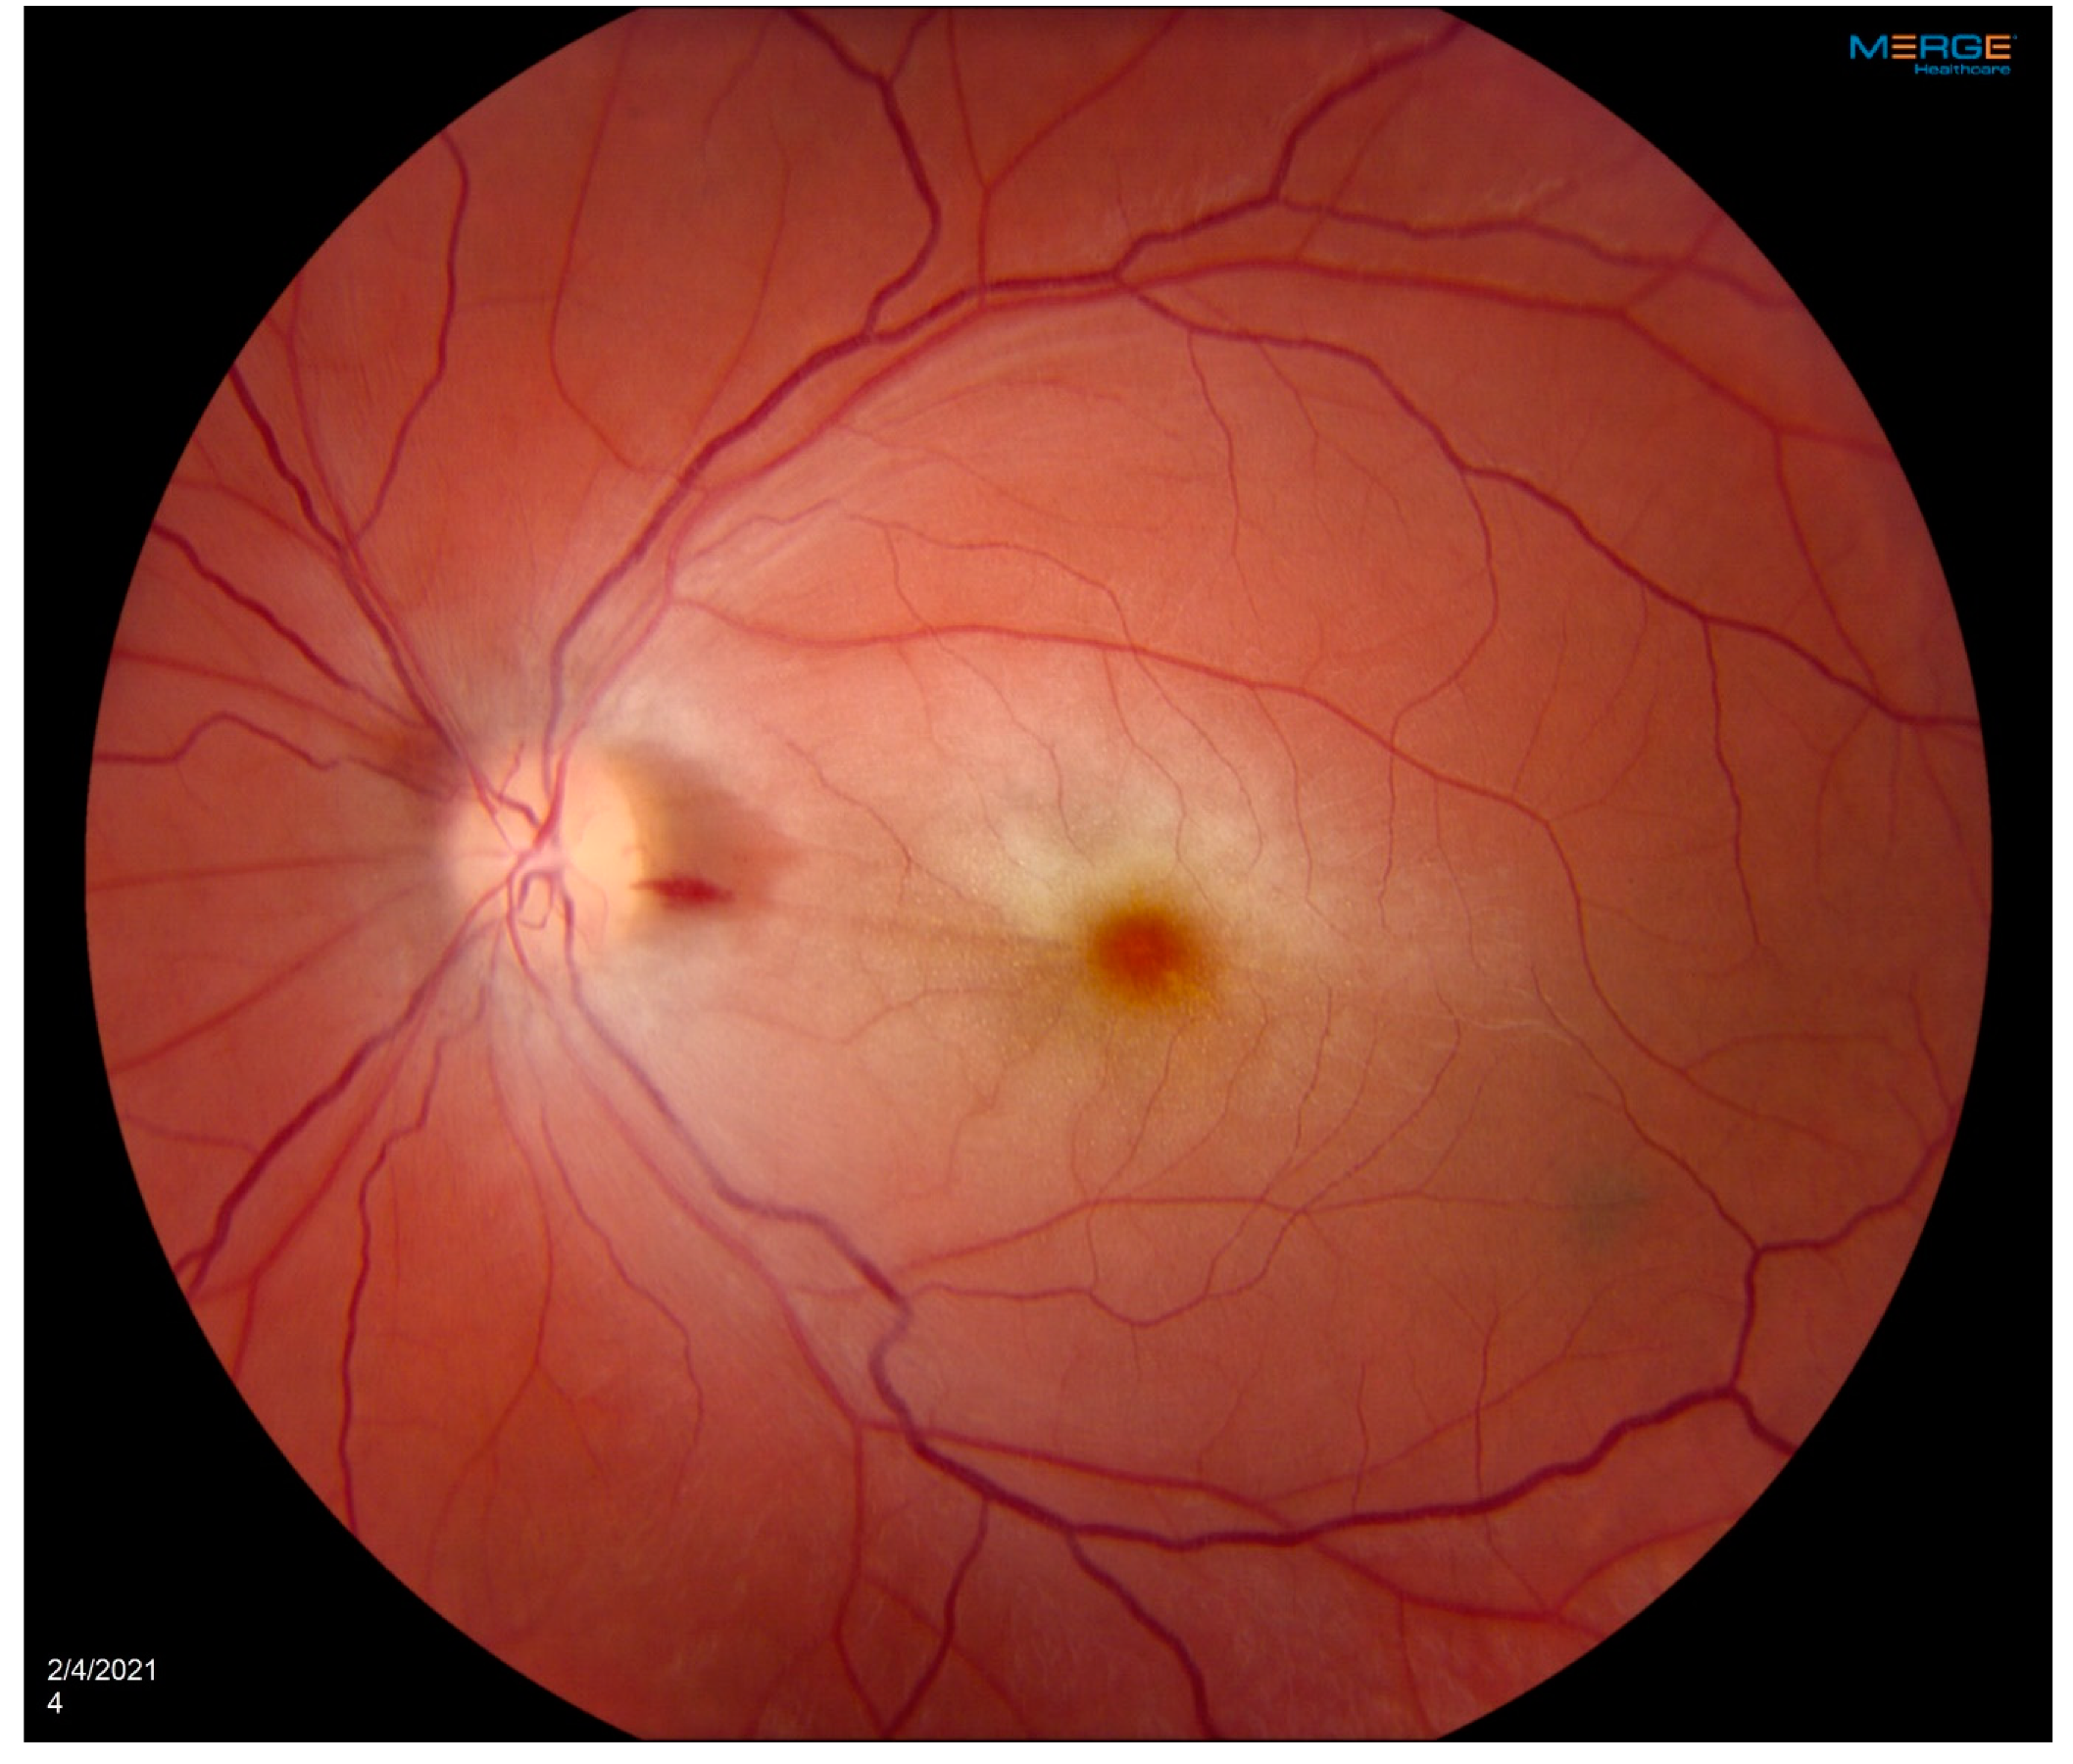

Figure 1. OS Fundus phorograph showing Central retinal artery occlusion with characteristic cherry red spot and attenuated blood vessels. Patient developed left central retinal artery occlusion years prior to the vasculitis diagnosis with loss of vision at a young age.

A 35-year-old woman with a prior history of left central retinal artery occlusion and bilateral sensorineural hearing loss concerning initially for neurosarcoidosis (never histologically proven) presented for clinic follow-up. She had a complicated disease course dating back many years involving different specialists including fluctuating hearing loss partially responsive to corticosteroids necessitating cochlear implants and developed central retinal occlusion of the left eye (Figure 1 and Figure 2). This was concerning for possible underlying inflammatory condition such as neurosarcoidosis or Susac syndrome (MRI atypical sans corpus lesion) and she received IV immunoglobulin treatment. When she returned for follow-up, she had complaints of episodes of confusion, but quiescent symptoms without visual change, status post adalimumab and methotrexate addition. She sought emergency care for new transient arm numbness and confusion and CTA neck revealed carotid bulb circumferential thickening suggestive of vasculitis (Figure 3, Figure 4 and Figure 5). The patient was initiated on Infliximab with IV methylprednisolone and close follow-up with neurology and vascular medicine for management of Takayasu arteritis.